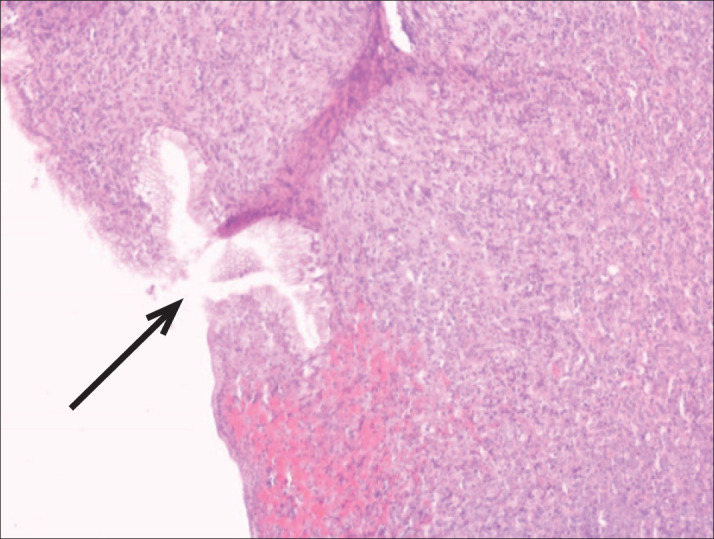

Background: Burkitt's lymphoma (BL)belongs to the group of lymphomas with an aggressive clinical course. It is a rare form of lymphoma in adults with an incidence of 1200 patients per year in the USA.

Objective: The aim of this article was to present for the first time the case of a patient in whom Burkitt's lymphoma was proven by biopsy and curettage of the uterus, and at the same time in the biopsy of palatine tonsil and bone.

Case report: A 64-year-old female patient who comes because of difficulty in swallowing, enlarged neck lymph nodes and vaginal bleeding. Under diagnosis Lymphoma non Hodgkin Burkitt CS IV B, ECOG 3, IPI 5 (high risk), R-IPI:5 (poor prognostic index) introduction of IHT R-CHOP 4 cycles with therapeutic response.